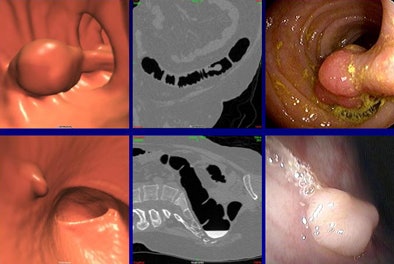

| Discordant findings included a 12-mm flat cecal lesion (top row) with contrast coating, diagnostic confidence 2, that was not visualized at optical colonoscopy. Bottom row, a 14-mm flat lesion (confidence level 3) was not seen at initial optical colonoscopy, but was confirmed at follow-up VC and optical colonoscopy. |